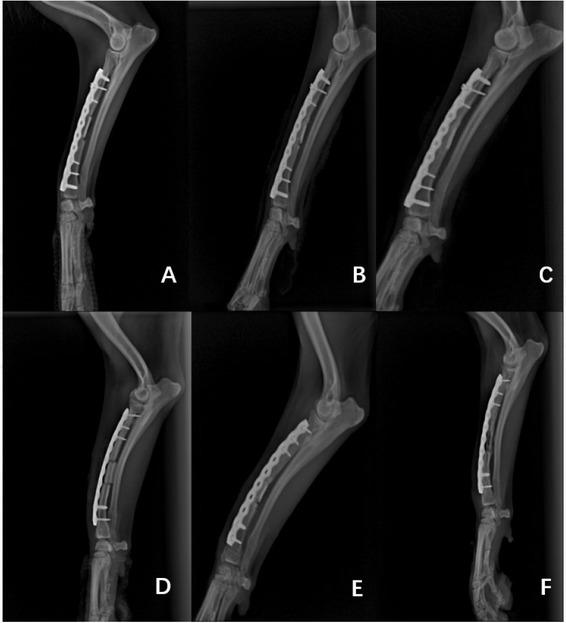

Fig. 1